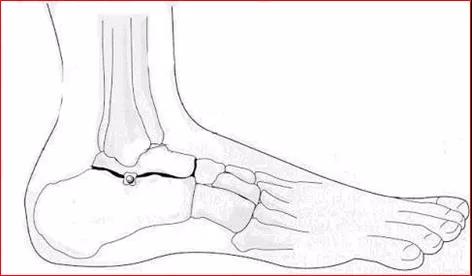

踝关节穿刺术

体位:仰卧,踝关节轻度跖屈定位:胫前肌腱与内踝之间

穿刺:针尖指向外后方